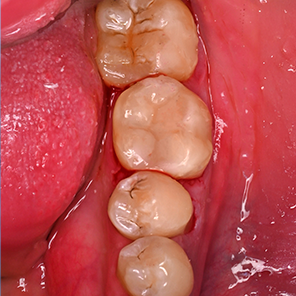

연세일등치과는 충치를 단순히 메우는 것보다

치아의 남은 구조를 얼마나 많이 보존할 수 있을지를

먼저 생각합니다.

치아

이를 위해 치료 전 단계부터 정밀한 진단을 통해

건강한 부위와 손상된 부위를 구분하고,

치료 범위를 필요한 만큼만 설정합니다.

연세일등치과는 최대 보존을 단순한 목표가 아닌

정밀한 진단과 설계의 결과물로 봅니다.

건강한 부위와 손상 부위를 면밀히 구분하고,

필요한 만큼만 조심스럽게 다듬어

치아 본연의 구조를 최대한 보존하는 치료를 진행합니다.